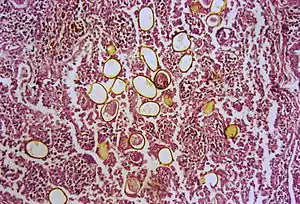

The first human case was seen in 1879 in Taiwan. An autopsy was done and adult trematodes were found in the lungs. The adult flukes have a reddish-brown in color with an ovoid shape. They have two muscular suckers, the first an oral sucker located anteriorly and the second a ventral sucker located mid-body. The adult flukes can live up to 20 years. The eggs are golden brown in color and are asymmetrically ovoid. They have a very thick shell. As seen above, these trematodes have a very complex life cycle with seven distinct phases involving intermediate hosts and humans.[15] These seven phases are outlined as follows: eggs reach fresh water where they develop into miracidia. These penetrate many species of aquatic snails (first intermediate host) where they go through three distinct stages: first sporocysts, then rediae, and finally cercariae, also referred to as the larvae. These larvae released into water and penetrate crabs, crayfish and other crustaceans (second intermediate host). The cercariae situate themselves into the gills, liver and muscles where they further develop into metacercariae. When the parasite-filled crustacean is eaten, the metacercariae hatch in the intestine. These young worms penetrate intestinal wall, peritoneum, the diaphragm and the pleura where they finally reach the lungs. Here they live in pairs, lay eggs that are coughed up in sputum to restart the cycle.[16]